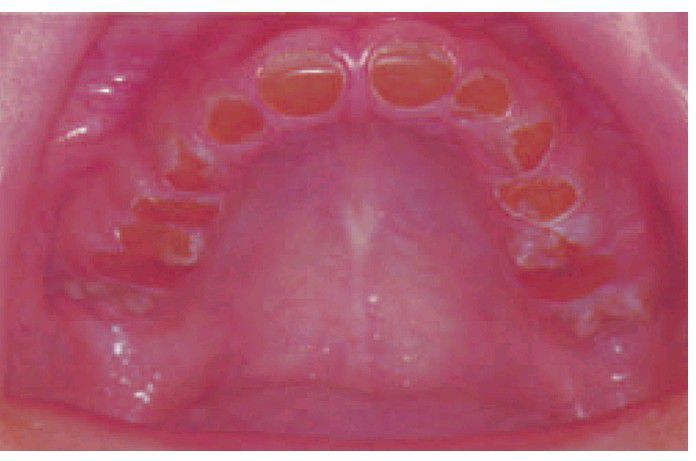

Dentinogenesis imperfecta.

In this 14-year-old, the teeth have worn down to gingival level but the pulp chambers have become obliterated as part of the disease process. Some enamel remains around the necks of the posterior teeth.